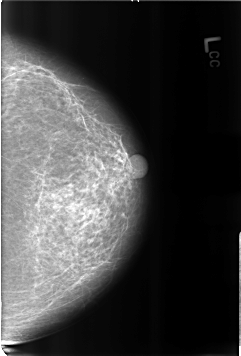

B_3180_1.LEFT_CC

LEFT_CC LINES 4616 PIXELS_PER_LINE 3128 BITS_PER_PIXEL 12 RESOLUTION 50 NON_OVERLAY